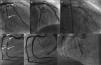

Coronary angiography showing (A) 85% long stenosis of the first obtuse marginal branch and 80% stenosis of the distal circumflex (CX) artery (arrows); (B) these lesions treated with two and one drug-eluting stents (DES), respectively; (C) the CX with gadolinium contrast after six months; (D) early right coronary artery (RCA) bifurcation, 90% stenosis of the right posterolateral branch (RPL) (arrows), 90% at the origin of the posterior interventricular artery (PIA) and 80% distal to the PIA; (E) these lesions treated with two DES in the RPL, one DES at the origin of the PIA and another in the distal segment of the PIA; (F) coronary angiography of the RCA with gadolinium contrast after six months. CX: circumflex artery; OM1: first obtuse marginal branch; PIA: posterior interventricular artery; RPL: right posterolateral branch.

The patient's platelet count returned to normal four days after the procedure. Prasugrel was then administered for three days without affecting the platelet count. Using 213 ml of ioxaglate sodium/ioxaglate meglumine ionic iodinated contrast (Hexabrix) and bivalirudin as an anticoagulant, percutaneous intervention was performed to implant seven zotarolimus-eluting stents (Figure 1B and E). After six hours, blood tests showed a platelet count of zero with no clinical manifestations; methylprednisolone was then administered gradually, and the platelet count recovered to 181×109/l after six days. The patient was diagnosed with severe thrombocytopenia after administration of iodinated contrast media.

Six months after revascularization, the patient was readmitted with angina symptoms. He opted for conservative management and intensified treatment. However, he was readmitted three weeks later with refractory rest angina, and was referred for coronary angiography. After being informed of the risk of nephrogenic systemic fibrosis (NSF), the patient agreed to the procedure. Gadolinium (gadoteridol) was used as a contrast medium, using only 36 cc, and IVUS studies indicated severe restenosis of the previously implanted stents in the first obtuse marginal branch and the right coronary artery (Figures 1C and F and 2A and C). Coronary surgery was proposed and rejected by the heart team, so percutaneous revascularization was performed in two stages (Figure 2B and D), using 42 cc of gadoteridol in each procedure and hemodialysis four hours after the procedure to reduce the risk of NSF. Platelet counts were unchanged after these procedures, confirming the diagnosis of thrombocytopenia induced by iodinated contrast. No adverse events were reported on admission. After two years of follow-up, the patient has had no unstable angina pectoris and has not developed signs or symptoms suggestive of NSF.

Coronary angiography with gadolinium contrast assessed by intravascular ultrasound showing significant stenosis (arrows): (A): in-stent restenosis (ISR) of the first obtuse marginal (OM1), subocclusive stenosis of the distal circumflex (CX) artery and at the origin of the OM1; (B) ISR treated with a paclitaxel-eluting balloon, and both stenoses treated by double-kissing crush stenting with two drug-eluting stents (DES) at the origin of the OM1 and CX; (C) ISR of the right posterolateral branch (RPL), of the distal edge of the distal stent of the PIA, and of the proximal stent segment of the posterior interventricular artery (PIA), affecting the proximal right coronary artery (RCA); (D) the RPL treated with a paclitaxel-eluting balloon, the distal PIA with one DES, and the proximal PIA of the RCA with a balloon and one DES, ending with double-kissing crush stenting from the PIA to the RPL. CX: circumflex artery; MLA: minimal lumen area; OM1: first obtuse marginal branch; PIA: posterior interventricular artery; RPL: right posterolateral branch.